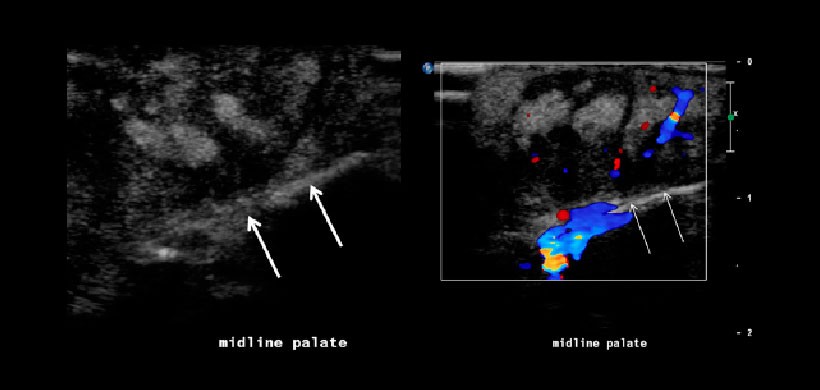

Fig 3. Paciente de 51 años, que presentaba una masa exofítica de aproximadamente 2,3 cm de diámetro. A) y B) En la ultrasonografía Doopler se evidenció una lesión sólida, de ecogenicidad heterogénea la lesión no estaba bien definida., cuya extensión llega al maxilar, antro o la fosa nasal. El flujo Doppler demostró que la lesión es altamente vascular, con muchas vasos pulsátiles (Figura 3b). Los signos mostraban una lesión altamente sospechosa de malignidad; por lo tanto, se procedió a la realización de un resonancia magnética y de la biopsia por incisión. La biopsia confirmo que se trataba de un carcinoma adenoide quístico.